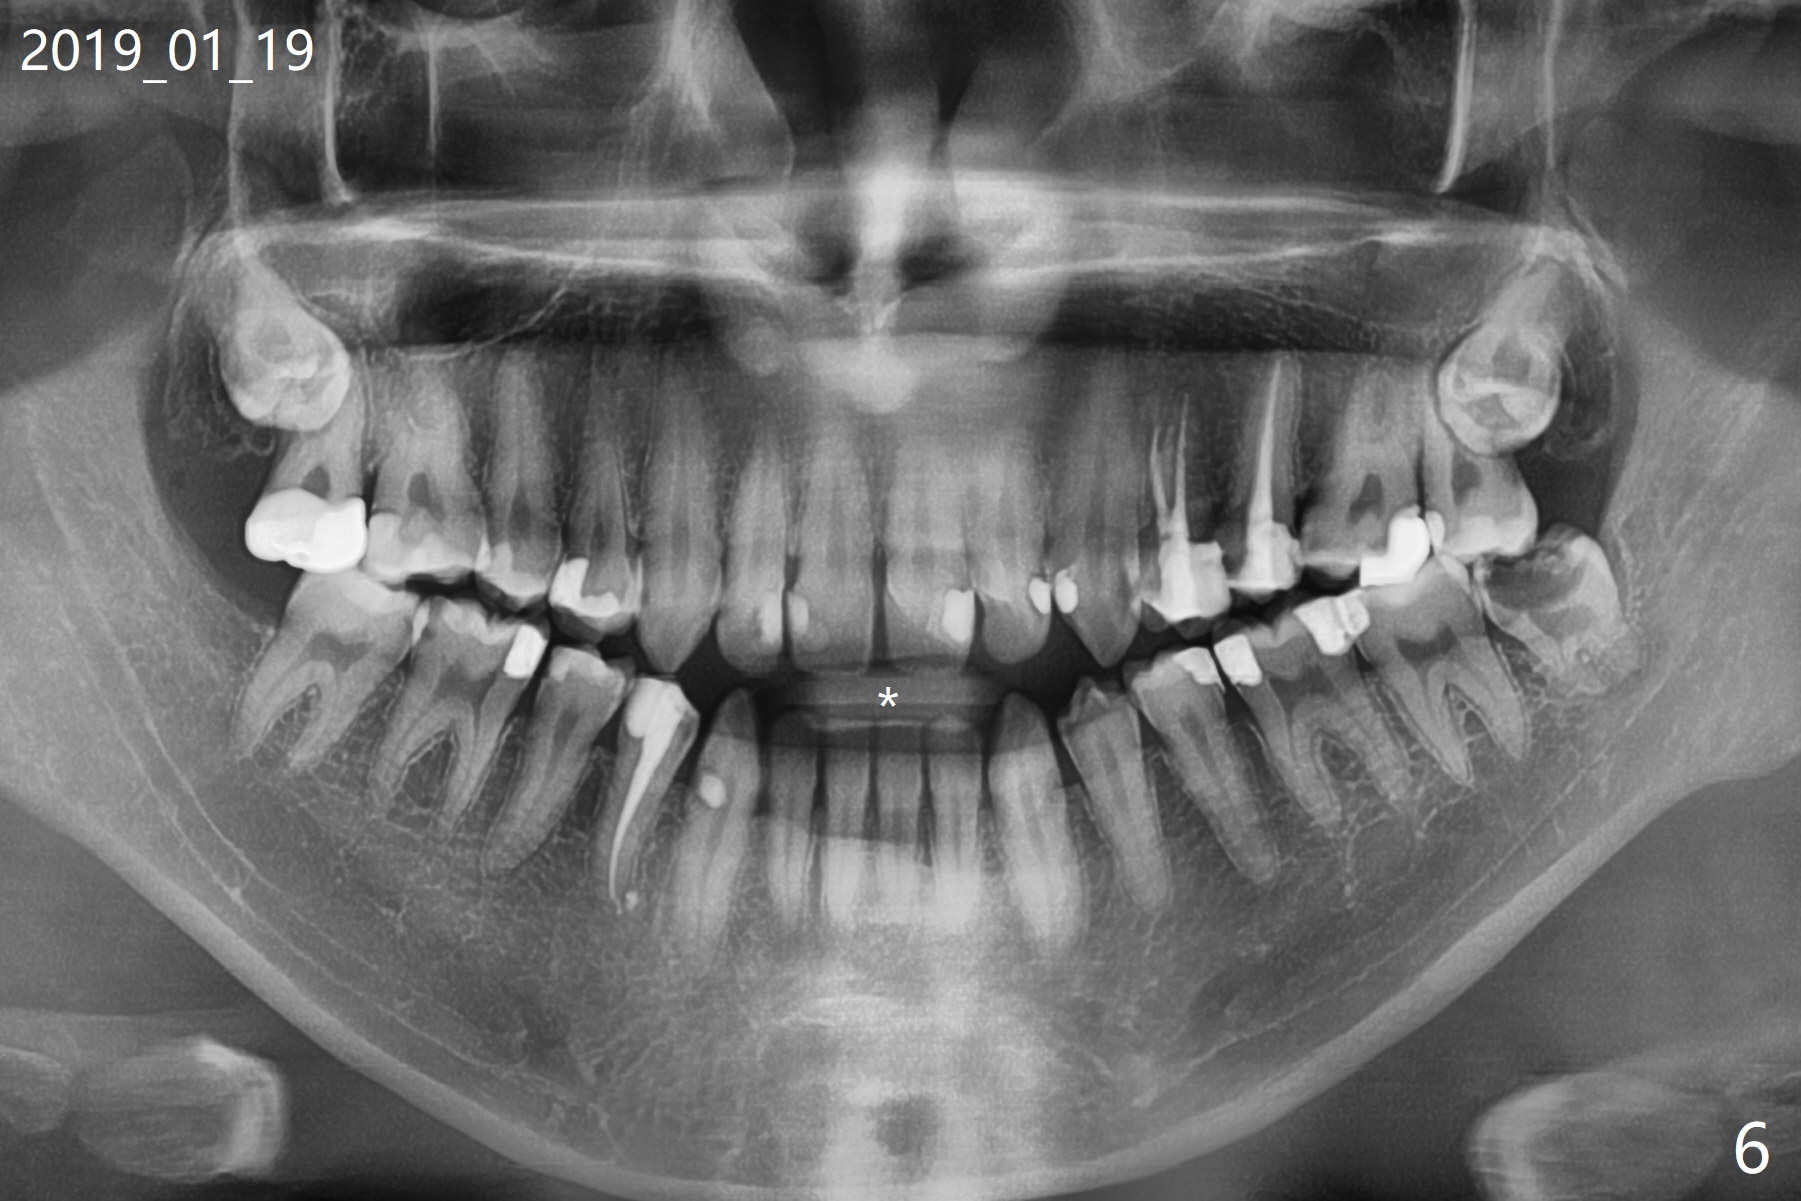

8阻生牙可能迫使7延长(图五:箭头),可能造成前牙开合(图六:*),总之,左上8必须拔除(图七),其实必须两次手机切开才能去除。可能还需要拔除右上8,然后全口牙齿矫正。